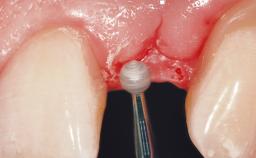

Immediate Flapless Placement of an Implant in a Maxillary Left Central Incisor Site

A 29-year-old female patient presented for treatment to replace the upper left central incisor tooth with an implant- supported restoration. The tooth had been intermittently symptomatic for the previous 12 months. The tooth had originally suffered trauma about 15 years previously. Several endodontic treatments had been performed, including an apicectomy procedure to retain the tooth. The patient was healthy and a non-smoker. She had reasonable expectations in regard to esthetic outcomes and the risk of marginal tissue recession following treatment. At medium smile, the gingival margins of the upper teeth were visible, with a display of 3 to 4 mm of the gingival margins. Gingival recession of tooth 21 and a discrepancy in the gingival levels between teeth 11 and 21 was observable during normal speech and smile.

| Soft Tissue Contour and Volume | Slightly compromised |